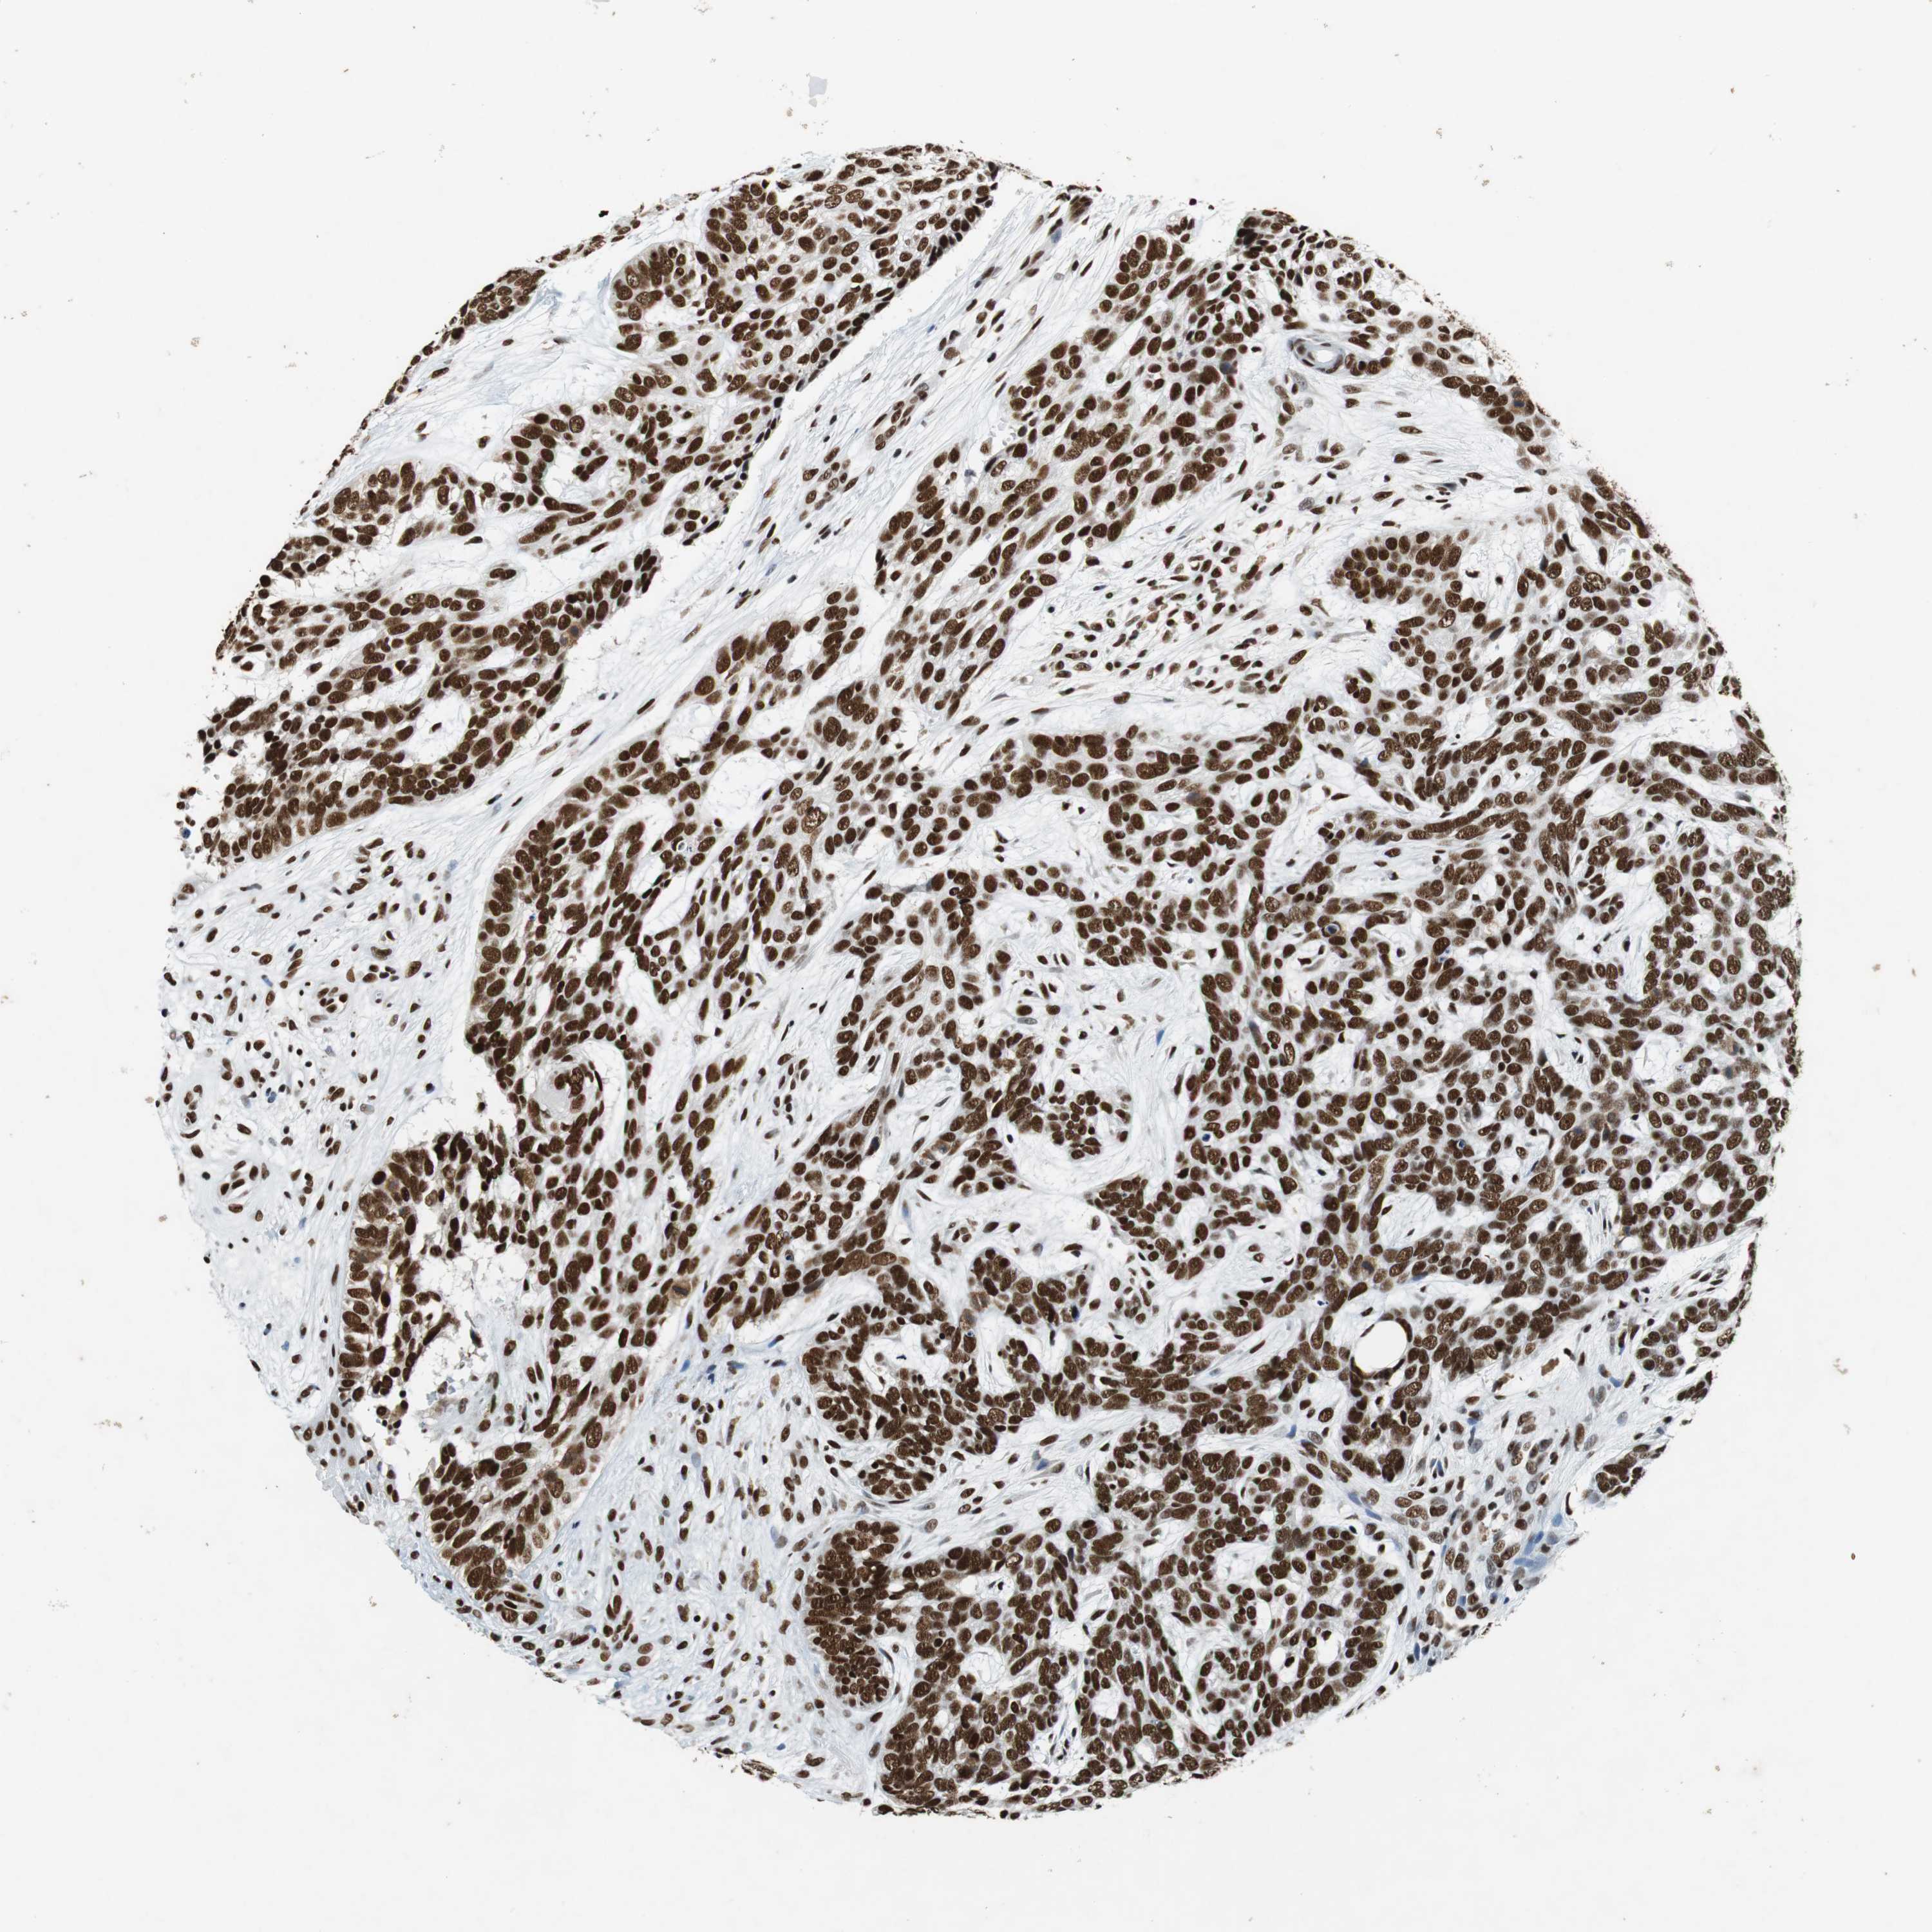

Basal cell and squamous cell cancer

SKIN CANCER - Protein expressioni

A mouse-over function shows sample information and annotation data. Click on an image to view it in a full screen mode. Samples can be filtered based on level of antibody staining by selecting one or several of the following categories: high, medium, low and not detected. The assay and annotation is described here.

Antibody stainingi

Antibody staining in the annotated cell types in the current human tissue is reported as not detected, low, medium, or high, based on conventional immunohistochemistry profiling in selected tissues. This score is based on the combination of the staining intensity and fraction of stained cells.

Each image is clickable and will lead to virtual microscopy that enables deeper exploration of all samples and also displays staining intensity scores, fraction scores and subcellular localization as well as patient and tissue information for each sample.

Antibody HPA035174

Antibody CAB005167

Staining

High

Medium

Low

Not detected

Intensity

Strong

Moderate

Weak

Negative

Quantity

>75%

75%-25%

<25%

None

Location

Nuclear

Cytoplasmic/membranous

Cytoplasmic/membranous,nuclear

Squamous cell carcinoma, NOS